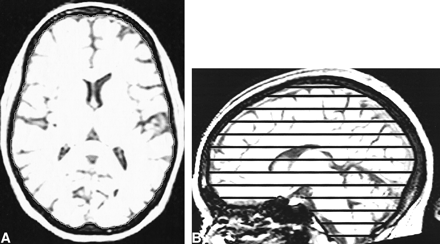

The TIV measure we employed uses T1-weighted volumetric images put into the orientation defined by the Montreal Neurological Institute 305 brain average (25) using 3D registration. The method used to delineate the TIV is analogous to that described above, except the semiautomatic gray level thresholding technique was set at a standard threshold of 33% of the mean intracranial signal intensity to outline the outer border of dura (Fig 1A); this reflects the different contrast in the T1-weighted image compared with the T2-weighted image. Every 10th axial section was segmented with the inferior border set as the lowest section in which cerebellar tissue was present (Fig 1B). Linear interpolation of areas was used to obtain an estimate of the TIV from the segmented sections. This method is supported by Eritaia et al (26), who evaluated various sampling strategies to measure a TIV from T1-weighted images and concluded that the TIV can be confidently traced by using a 1-in-10 section strategy without significant loss of accuracy. The T1-weighted TIVs were initially measured on two serial images from a group of five AD patients and five controls, to compare with the T2-weighted TIVs and to look for variability over serial images. The T1-weighted TIVs and brain volumes then were measured on multiple serial images of five AD patients with short imaging intervals, 10 controls, and the two people at risk of familial AD.

T1-weighted MR images with sagittal and axial views. The intensity windowing is as used for segmentation. The TIV is calculated by summation and linear interpolation of the segmented axial slices.

A, The total intracranial area is shown on one axial section.

B, The axial sections used to sample the total intracranial volume are marked on the sagittal view.